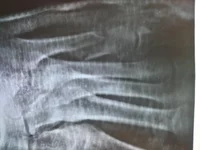

Перелом со смещением

Сломал кость, которая сразу за мизинцем левой ноги.

Вправили, сделали гипсовую шину. Прошла неделя и контрольный снимок показал незначительное смещение. Врач сказал, что все в пределах нормы. Опухоль спала и перестала держать кость. И если еще через неделю смещение окажется сравнительно большим, возникнет необходимость хирургического вмешательства. Но раз уже немного смещено, может нет смысла ждать еще неделю?

И существует ли альтернативная возможность как-нибудь выпрямить кость без хирургического вмешательства?